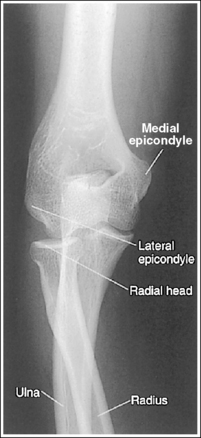

The elbow has been externally rotated 45 degrees. The capitulum and radial tuberosity are demonstrated in profile, the radial head, neck, and tuberosity are visualized without superimposing the ulna, and the radioulnar articulation is demonstrated.

• Accurate positioning for an externally rotated AP oblique elbow projection is achieved by positioning the arm in an AP projection and then externally rotating the humerus and forearm until the humeral epicondyles form a 45-degree angle with the IR (Figure 4-75). This positioning rotates the radius away from the ulna, demonstrating it without superimposition. If the humeral epicondyles are at less than 45 degrees of obliquity, the radial head and tuberosity still partially superimpose the ulna (see Image 85). If the humeral epicondyles are at more than 45 degrees of obliquity, the coronoid process is partially superimposed over the radial head, and the radial neck and tuberosity are free of superimposition; the radial tuberosity is no longer in profile (see Image 86).